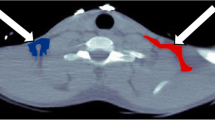

In order to generate myocardial time–activity curves (TACs), regions of interest (ROIs) were defined on resliced short-axis [11C]palmitate images using the OSEM reconstructed summed image from 10 to 30 min. Six basal ROIs, six distal ROIs and one apical ROI were defined as described previously [17]. Additional ROIs were defined in left ventricular chambers for image-derived input functions (IDIF). An example of ROI placement is shown in Fig. 1. Myocardial segments exposed to liver spill-in were omitted from the analysis of [11C]palmitate scans, whilst all other ROIs were grouped for further analysis. All ROIs were projected onto the dynamic H2 15O image data to generate water TACs.